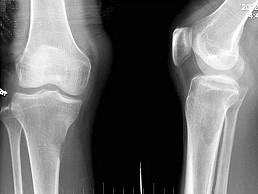

问题 男,59岁,右小腿近端疼痛1年,活动障碍半年,结合图像,最可能的诊断是?(?)

选项 A.右胫骨结核 B.右胫骨骨转移 C.软骨肉瘤 D.骨肉瘤 E.纤维肉瘤

答案 B